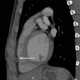

Retrosternal mass